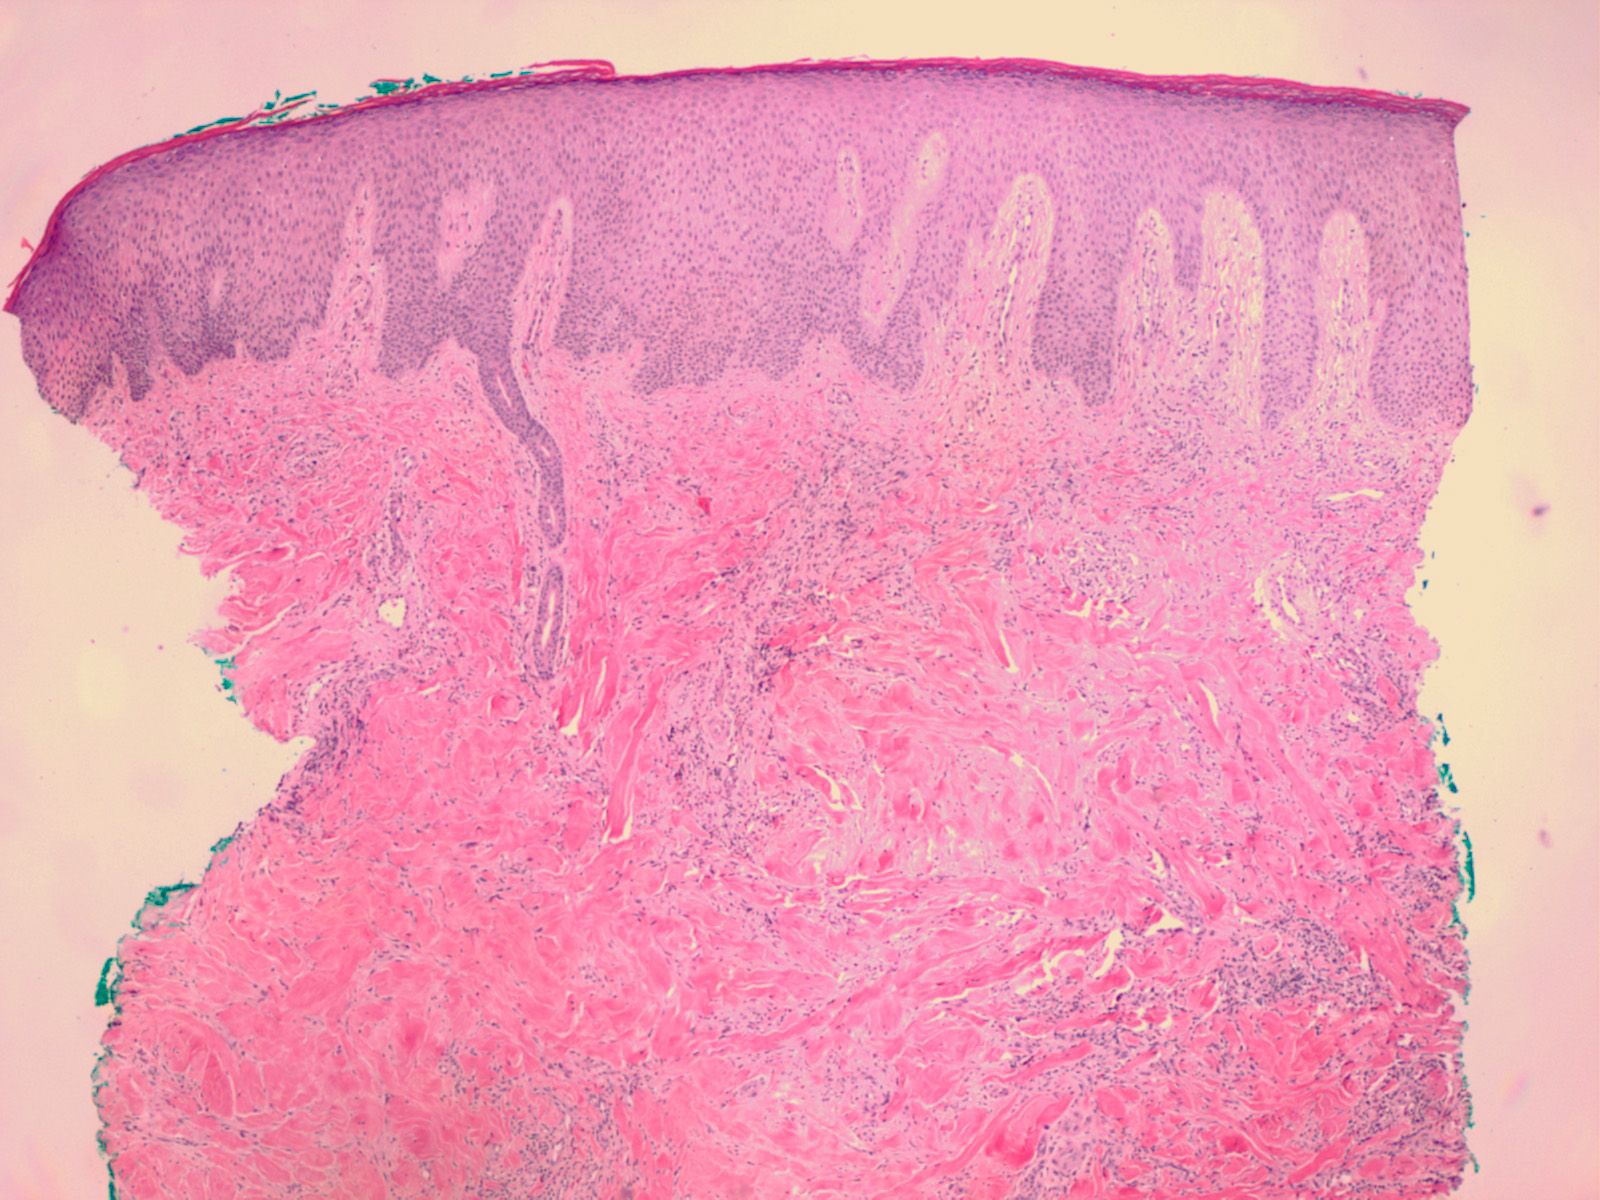

Atlas of skin histopathology